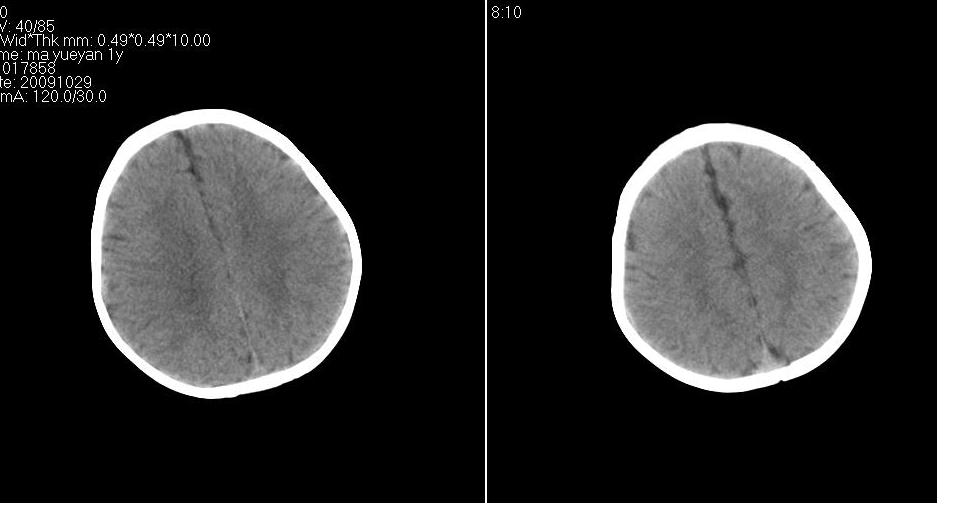

男 1岁,外伤就诊。智力正常,骨窗正常。

正常变异,大枕大池。鉴别:蛛网膜囊肿、双侧小脑发育不良。

蛛网膜囊肿一般是封闭的空间,张力较大,临近颅骨一般受压变薄。本例支持大枕大池

大枕大池与蛛网膜囊肿的主要区别就是看颅骨有没有压迹,如果有的话一般考虑蛛网膜囊肿。